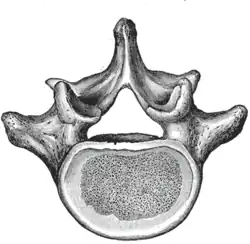

The adjacent figure depicts the general characteristics of the first through fourth lumbar vertebrae. The fifth vertebra contains certain peculiarities, which are detailed below.

As with other vertebrae, each lumbar vertebra consists of a vertebral body and a vertebral arch. The vertebral arch, consisting of a pair of pedicles and a pair of laminae, encloses the vertebral foramen (opening) and supports seven processes.

The vertebral body of each lumbar vertebra is kidney shaped, wider from side to side than from front to back, and a little thicker in front than in back. It is flattened or slightly concave above and below, concave behind, and deeply constricted in front and at the sides.[1]

The vertebral foramen within the arch is triangular, larger than the thoracic vertebrae, but smaller than in the cervical vertebrae.[1]